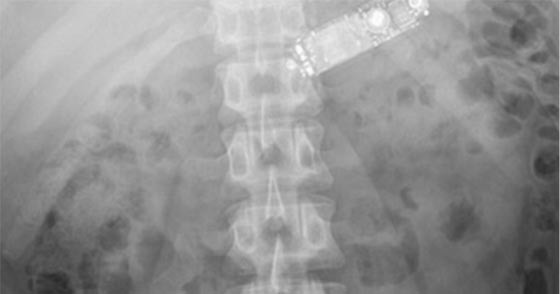

بعد أن ابتلع هاتفا في بطنه، ظل سجين إيرلندي يتقيأ أربع ساعات قبل أن ينقل إلى المستشفى. وواجه المسعفون حالة نادرة عندما وجدوا السجين البالغ من العمر 29 عاما في حالة يرثى لها. وأظهر فحص الأشعة السينية أن الهاتف موجود في داخل بطن السجين. وحاول المسعفون في بداية الأمر إخراج الهاتف عبر إدخال منظار طبي إلى جوف السجين، لكن هذه المحاولة أخفقت.

وأشاروا إلى أن الأمر يتطلب إجراء عملية شق البطن وإخراج الهاتف الذي استقر في المعدة، واستطاعوا في نهاية المطاف إخراج الهاتف من خلالها. وأظهرت الأشعة السينية ان الهاتف المحمول الذي ابتلعه السجين والبالغ من العمر 29 عاما سليم ولم يتأثر بالحامض المعدي. وقال أطباء لمجلة طبية إن هذه الحالة تشير إلى أن الحاجة ماسة إلى سرعة إجراء عمليات جراحية في حالات مماثلة. وأوضحوا أن ابتلاع الأجسام الصغيرة يمكن التخلص منها عبر المنظار، لكن في حالة الهاتف المحمول فإن الأمر يحتاج عملية جراحية.